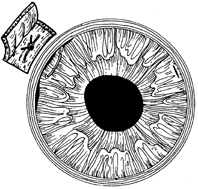

The goals in treating partial thickness corneal lacerations include preventing infection and promoting re-epithelialization and stromal healing. Every effort is made to minimize scarring and surface irregularity. If the wound edges are in good apposition with no wound gape, pressure patching with the use of prophylactic topical antibiotics is sufficient. Re-epithelialization is usually rapid. If the wound is unstable, a bandage soft contact lens may be used to support the wound and encourage re-epithelialization by minimizing the traumatic effect of lid movement (Fig. 2). Topical antibiotic prophylaxis, as well as cycloplegia for comfort, is used while the lens is in place. The lens should remain in place until wound healing is stable and complete re-epithelialization has occurred.